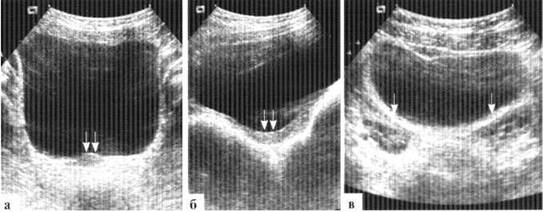

«Гипертрофированная» матка новорожденной в течении 1—3 месяцев подвергается инволюции, и в дальнейшем выглядит примерно одинаково как в 1 год, так и в 3, и в 6 лет. В этом возрасте суммарная длина матки с шейкой составляет около 3 см, ширина — около 1,5 см. Размеры матки у девочки только к 6—8 годам достигают размеров матки новорожденной (рис. 1.4). Постепенно изменяется и соотношение длины тела матки к шейке: к 4 годам оно достигает 1:1,7, к 7 годам 1:1,4, к 9 годам 1:1. Последняя цифра не точна: у некоторых девочек менархе наступает уже к 9 годам, внутренние гениталии уже имеют «взрослый» тип строения и это не считается патологией. Только к 8—9 годам начинает четко прослеживаться шеечно-маточный угол, который становится окончательно сформированным уже в пубертатном периоде. Примерно за полгода до наступления менархе матка начинает быстро увеличиваться в размерах, соотношение длины тела к шейке быстро достигает 2:1.

Размеры яичников у девочек нейтрального периода небольшие, составляют около 15x10 мм, могут дифференцироваться отдельные мелкие (до 3—4 мм) фолликулы. Довольно часто эхографически визуализировать яичники у девочек нейтрального периода не удается, и это не имеет самостоятельного клинического значения. К 7—8 годам в яичниках увеличивается количество фолликулов, размеры яичников достигают 20—25 мм в длину, 15 мм в ширину. Отдельные фолликулы могут достигать 7—10 мм в диаметре, число фолликулов может превышать 10 в каждом яичнике. Меняется топография яичников: они располагаются около углов матки.

Рис. 1.4. УЗИ внутренних гениталий у девочки 5 лет — «индифферентный тип»: а, б — поперечный и продольный сканы матки (двойная стрелка). Шеечно-маточный угол не выражен, толщина тела и шейки матки почти одинаковая, М-эхо не прослеживается; в — яичники (стрелки) содержат мелкие фолликулы, расположены высоко, визуализируются выше дна матки